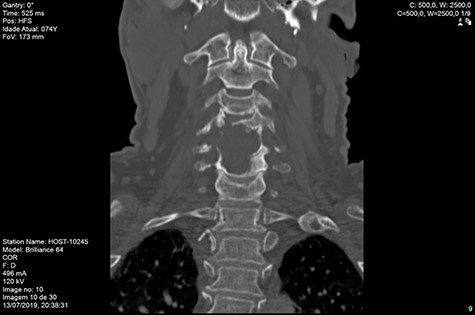

MRI and CT scans performed at 90 days post-radiation therapy showed an arrest of further progression of instability and resolution of the lytic lesion (Figs 7–13).